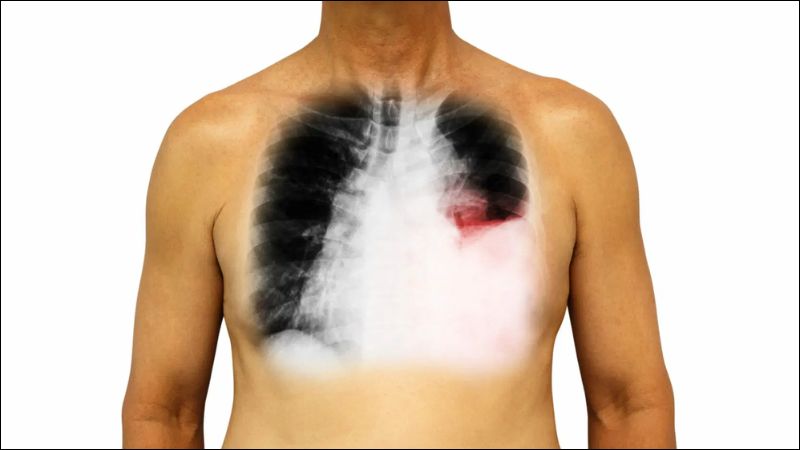

Bệnh lý về phổi

Các bệnh lý tại phổi như viêm màng phổi, tắc mạch phổi (cục máu đông trong phổi), hoặc thậm chí ung thư phổi cũng là những nguyên nhân gây đau ngực.

Người bệnh thường cảm thấy đau như dao đâm hoặc có cảm giác bị đè ép, cơn đau này sẽ tăng lên khi ho hoặc khi thở. Đặc biệt, nếu đau ngực khởi phát đột ngột kèm khó thở, đó có thể là dấu hiệu tắc mạch phổi, cần được cấp cứu y tế khẩn cấp.